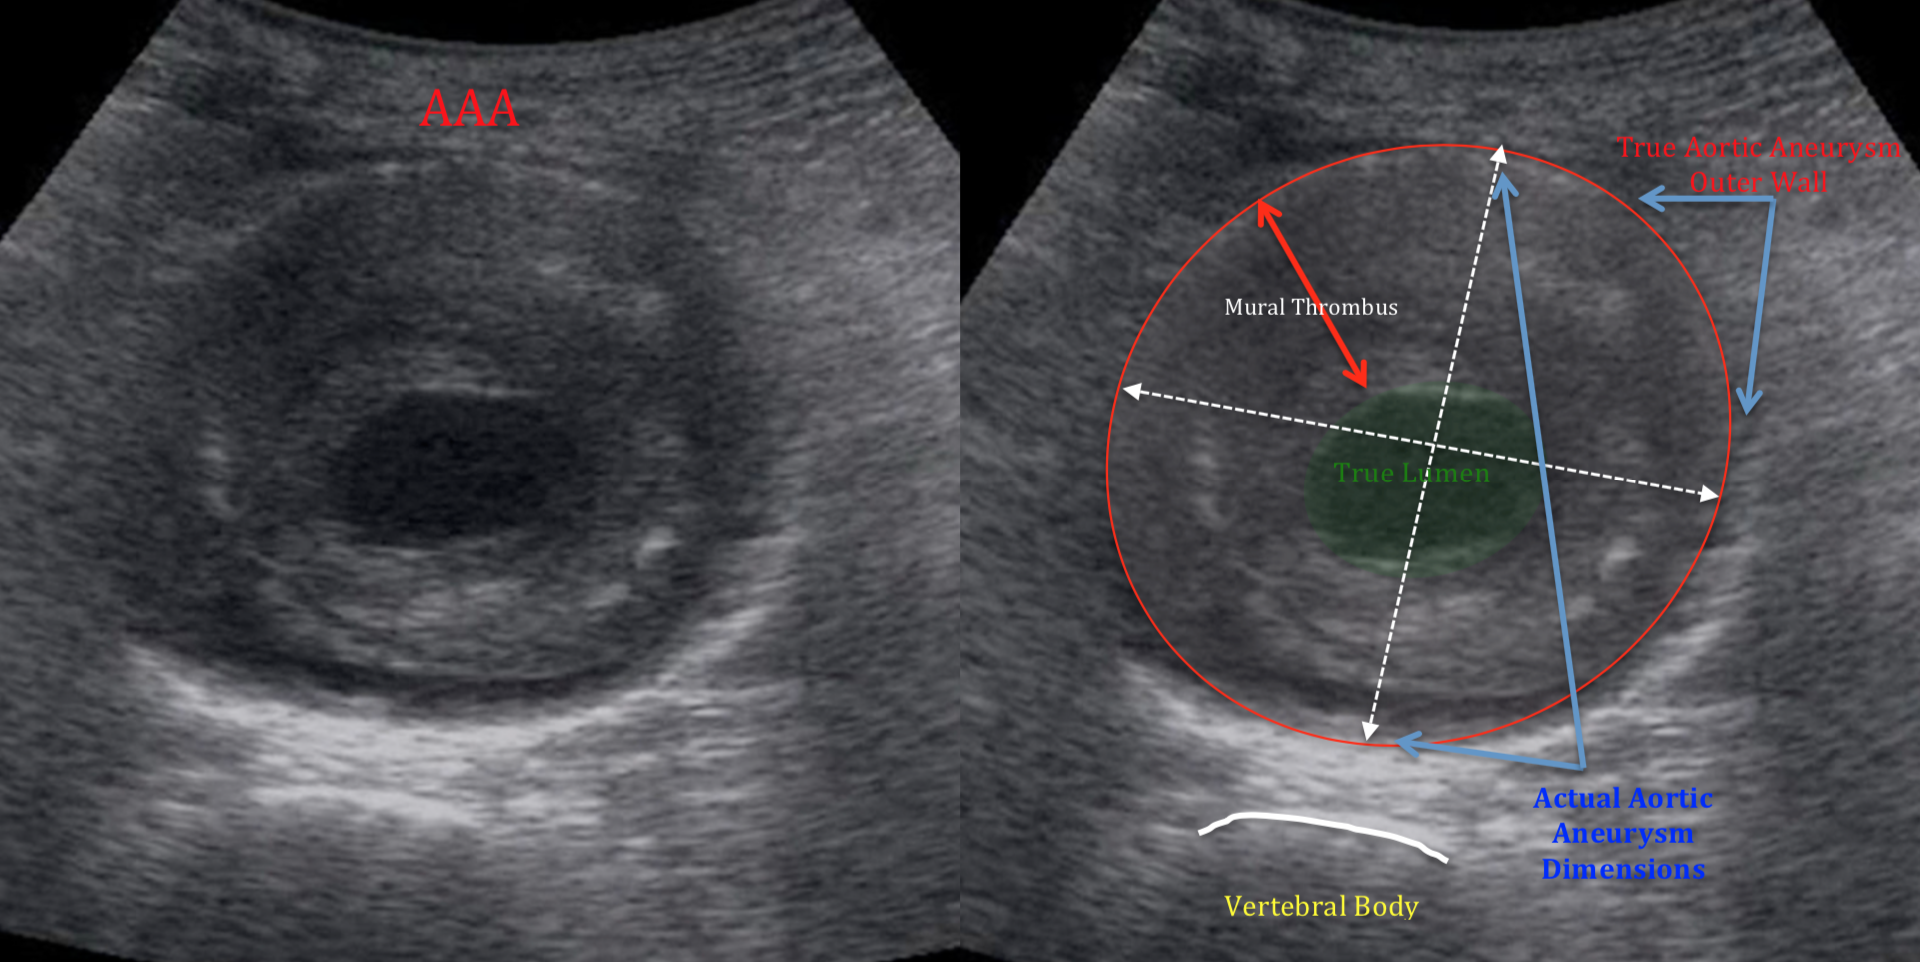

복부 대동맥류(AAA)

- 직경 3 cm 이상, 또는 정상 대비 50% 이상 확장된 상태를 말합니다.

- 5.5 cm 이상이면 파열 위험이 급격히 증가하므로 수술·스텐트 삽입을 검토합니다.

- 남성·흡연·고혈압·고지혈증·가족력이 주요 위험인자입니다.